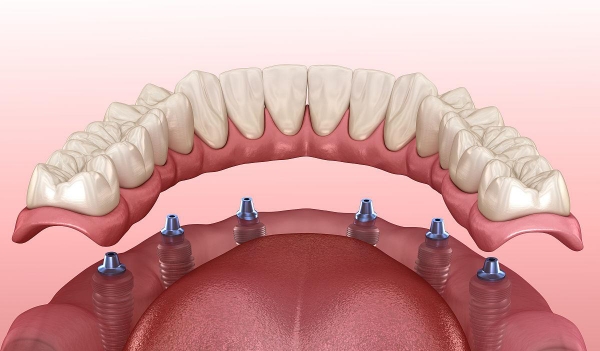

• ALL-ON-4/6即刻負(fù)重技術(shù):僅需4–6顆植體即可支撐整排牙齒,當(dāng)天種牙當(dāng)天吃飯